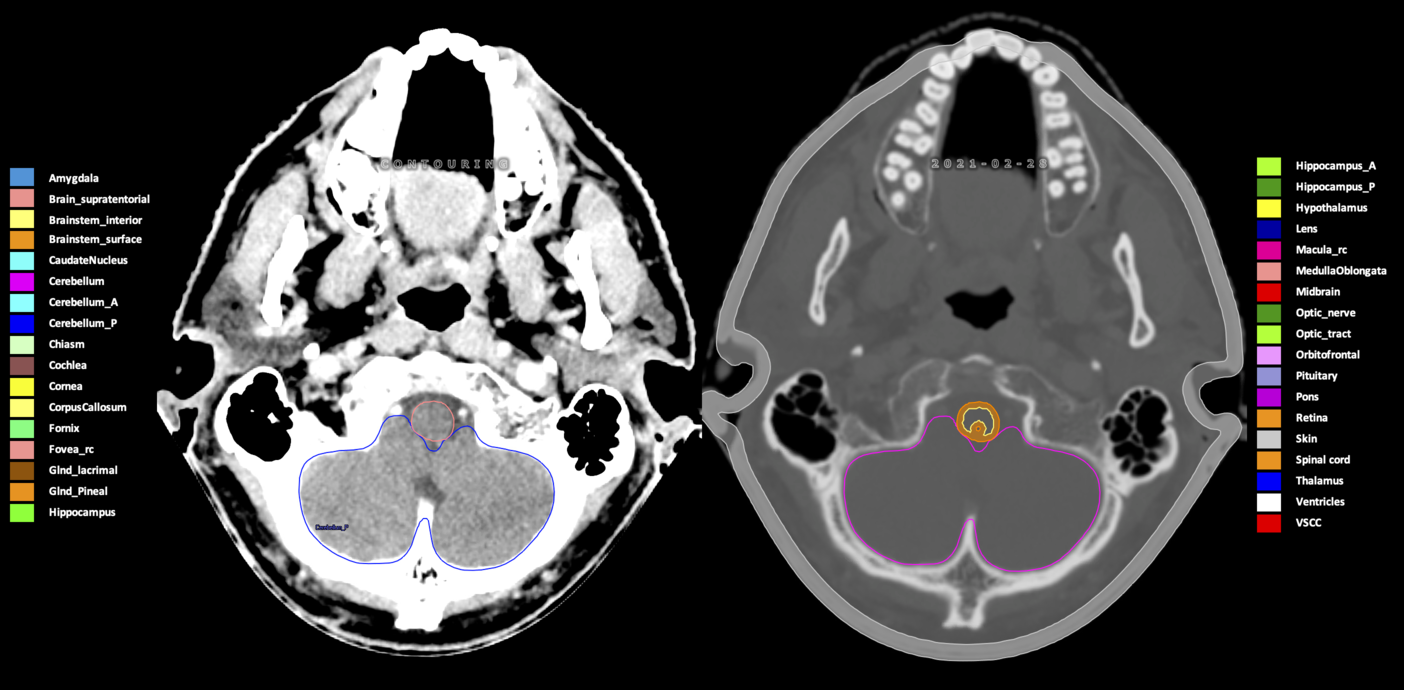

Included are all OARs known to be relevant for radiation-induced toxicity in neuro-oncology: brain, brainstem (midbrain, pons, medulla oblongata), chiasm, cerebellum (anterior & posterior), cochlea, cornea, hippocampus (anterior & posterior), hypothalamus, lens, lacrimal gland, optic nerve, pituitary, skin, and vestibular & semicircular canals. To further facilitate research on cognition, vision and radiological changes after irradiation of the brain, potential clinically-relevant OARs are included: amygdala, caudate nucleus, cerebellum (anterior & posterior), corpus callosum, fornix, macula, optic tract, orbitofrontal cortex, periventricular space (PVS), pineal gland, and thalamus.

Three-dimensional delineation of the 25 consensus OARs for neuro-oncology are shown on CT (WW/WL 120/40, 3000/600), 3T MR images, (T1Gd, T2FLAIR 1mm) and 7T MR (MP2RAGE 0.7 mm). All are presented in transversal, sagittal and coronal view.